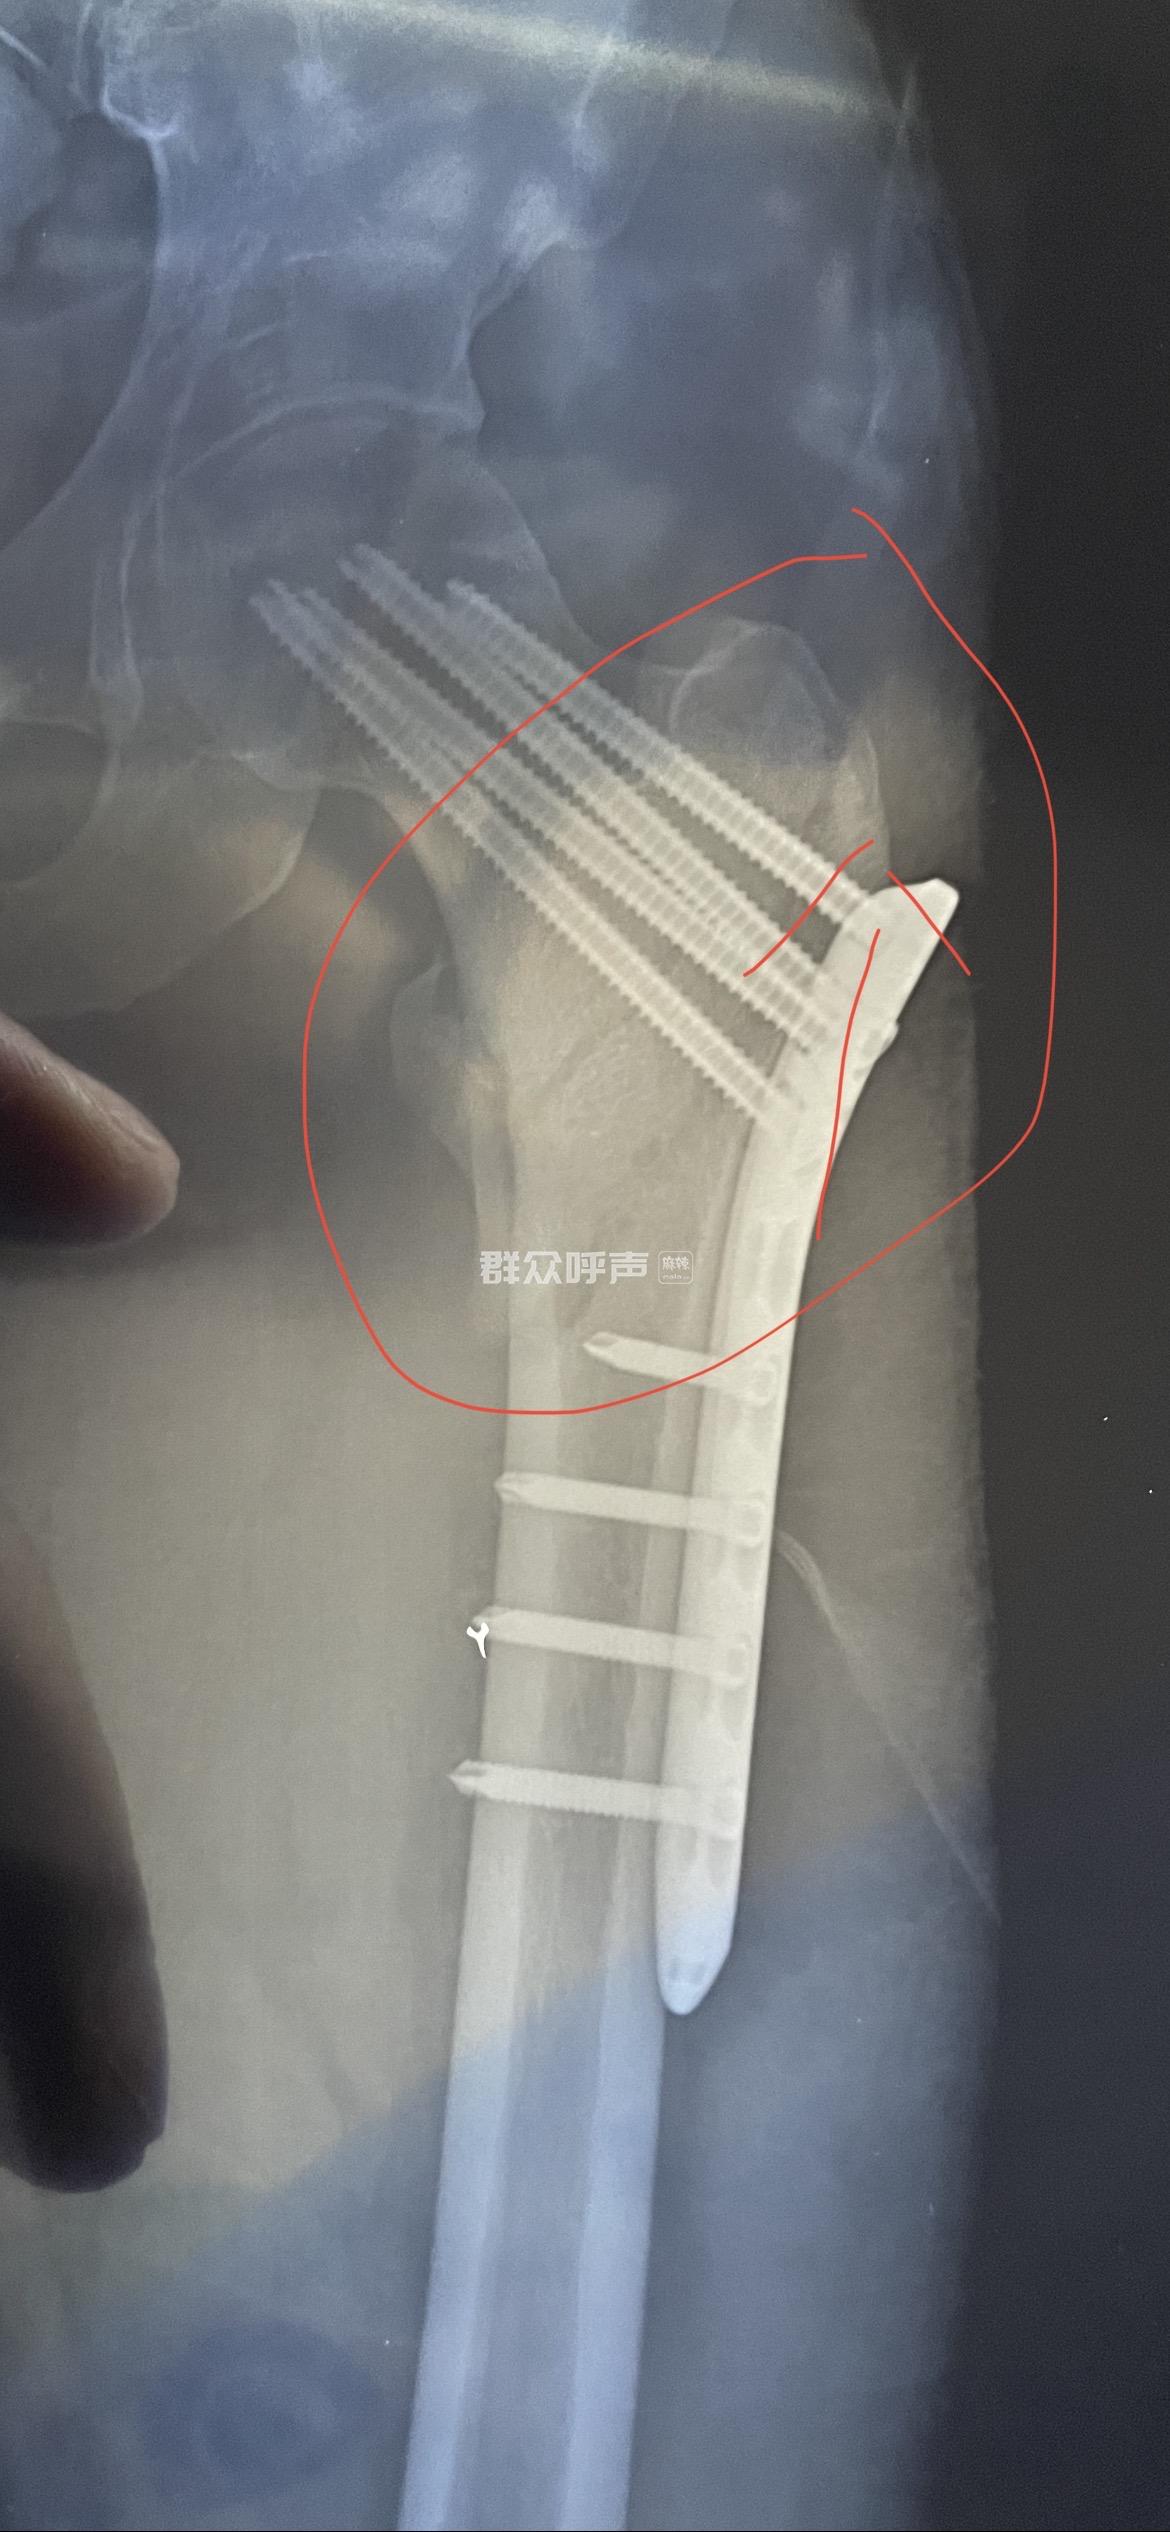

[求助] 工人意外摔落至工伤 公司不管不问